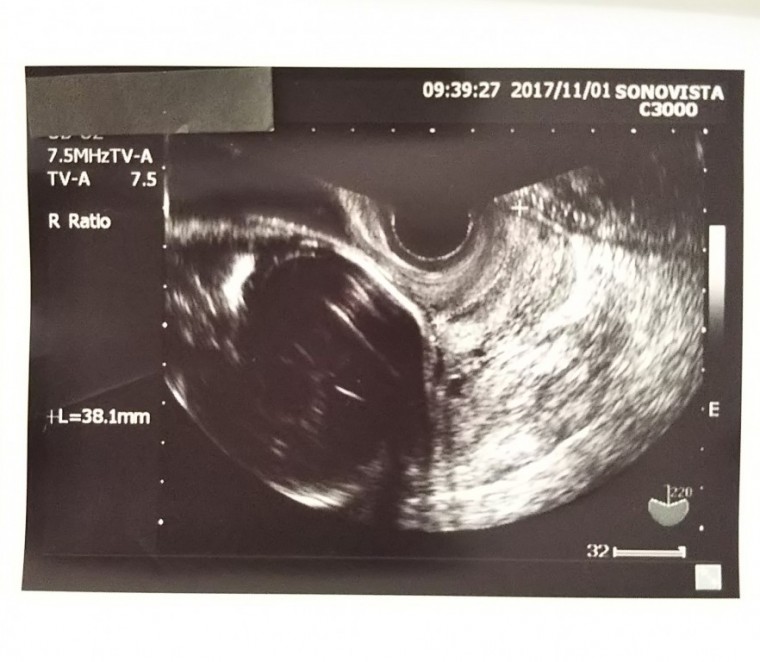

妊娠7ヶ月の超音波写真

妊娠7ヶ月(24週0日)撮影日:2017年11月01日

小粒ちゃん♡